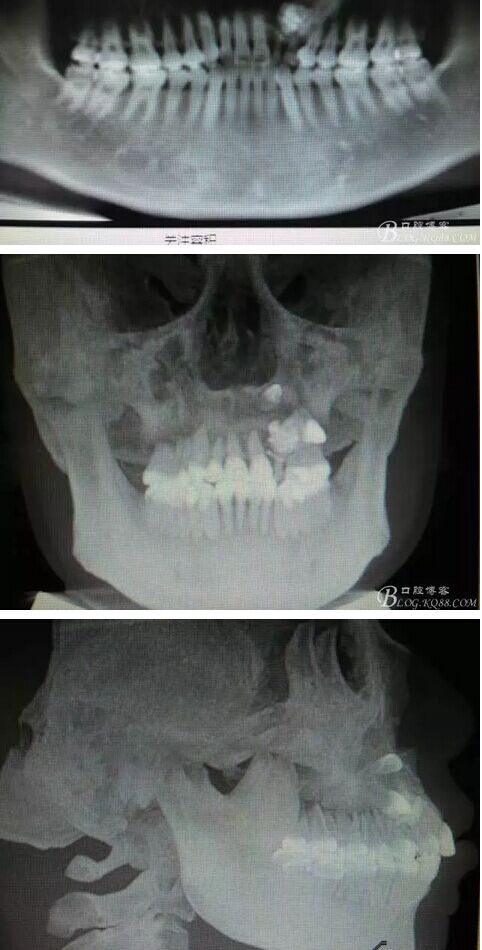

患者、女、曹xx、26歲,已婚。主訴:左側(cè)前牙區(qū)牙齦上有一疙瘩,要求治療。??茩z查:左側(cè)乳Ⅱ、Ⅲ滯留,頸部楔形缺損,探針不敏感。左側(cè)乳Ⅱ、Ⅲ唇側(cè)粘膜膨隆,表面結(jié)節(jié)狀,捫診質(zhì)地堅(jiān)硬,無波動(dòng)。CBCT檢查:左側(cè)乳Ⅱ、Ⅲ上方有一范圍約2.0x2.8cm的囊性改變,囊腔內(nèi)大量致密鈣化團(tuán)塊,密度高。22位于囊腔上方骨質(zhì)內(nèi),23移位至24上方區(qū)。診斷:1.牙瘤?2.牙瘤伴發(fā)囊腫?治療計(jì)劃:建議手術(shù)摘除?;颊咄馐中g(shù),并建議盡量保留左側(cè)乳Ⅱ、Ⅲ簽知情同意書。

圖1。術(shù)前的CBCT影像檢查:22位于鼻底下方,23位于24、25的根方。左側(cè)乳Ⅱ、Ⅲ根方顯示囊性改變,囊腔內(nèi)大量致密鈣化團(tuán)塊,密度高。